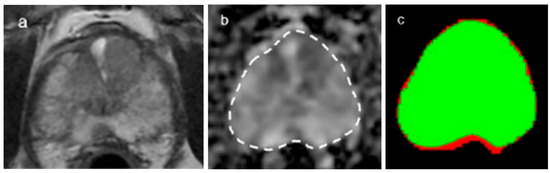

2.4. DL Architecture for Tumor and Gland Segmentation